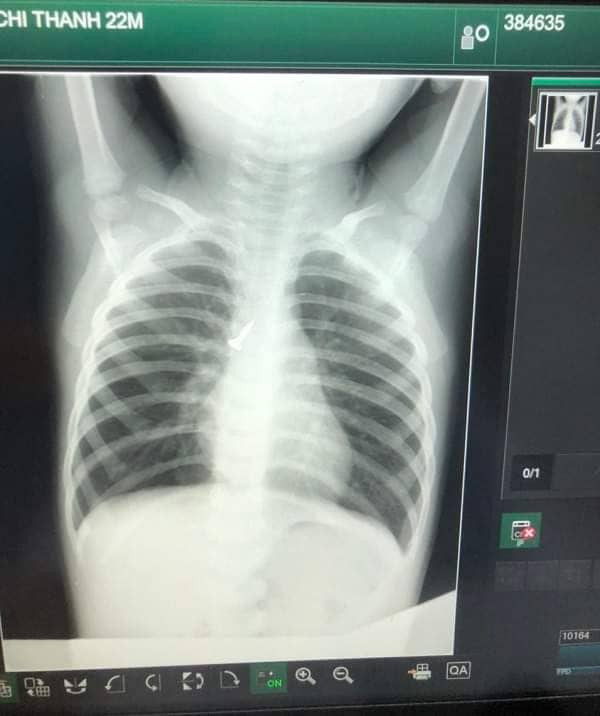

Tại đây, kíp trực cấp cứu đã khẩn trương cho chụp Xquang, làm các xét nghiệm máu, khí máu, phát hiện một dị vật hình ốc vít ở phế quản gốc bên phải, đầu nhọn hướng lên trên.